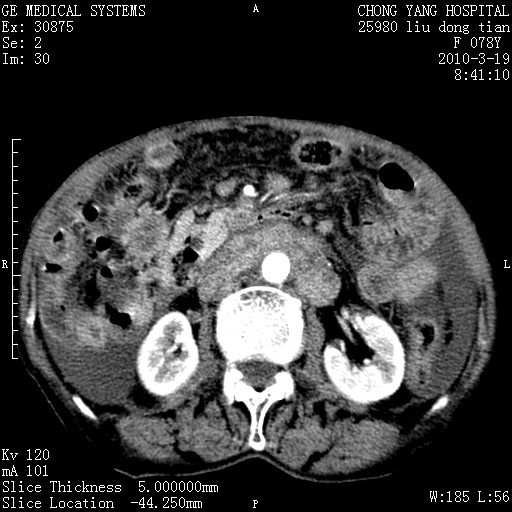

标题: CT25199:F 78Y 腹胀半年 消瘦乏力 [打印本页]

标题: CT25199:F 78Y 腹胀半年 消瘦乏力

胆囊壁增厚并明显强化,胆囊癌伴多发转移瘤可能性大,淋巴瘤不除外,右肾囊肿,胸腹水.

考虑nhl,肝、脾、腹膜腔及腹膜后多发淋巴结受侵,腹水,右肾囊肿,慢性胆囊炎,右侧少量胸腔积液。

首先考虑恶性淋巴瘤 。

胰头有肿块形成,胰头ca伴肝脾、腹膜腹膜后转移

胆囊有软组织影有强化,支持胆囊癌,肝脾、腹膜后淋巴结转移。

nhl的淋巴结多围绕主动脉,而且主动脉会移位,所以不考虑nhl。

分开来讲:肝左叶、尾叶病灶有不均强化像肝癌;

脾脏病灶无强化,像多发囊肿或淋巴管瘤,不除外淋巴瘤(低强化);

胆囊增生性病变:胆囊癌,腺肌增生症,慢性胆囊炎;

肝门、胰腺头、腹膜后多个团块: 淋巴瘤,转移;

腔静脉肝内段细小有无布加可能?

一元论最好了 淋巴瘤所致改变; 胆囊癌转移不像,胆囊周围肝组织清晰,肝癌淋巴结转移?三元论都不止。

脾脏病灶像车轮 莲花,第一感觉还像包虫呢。真想全切出来一个个做病检。

胰头ca伴肝脾、腹膜腹膜后转移!

最后报的胰头癌多发转移,脾脏单独考虑囊肿或淋巴管瘤。